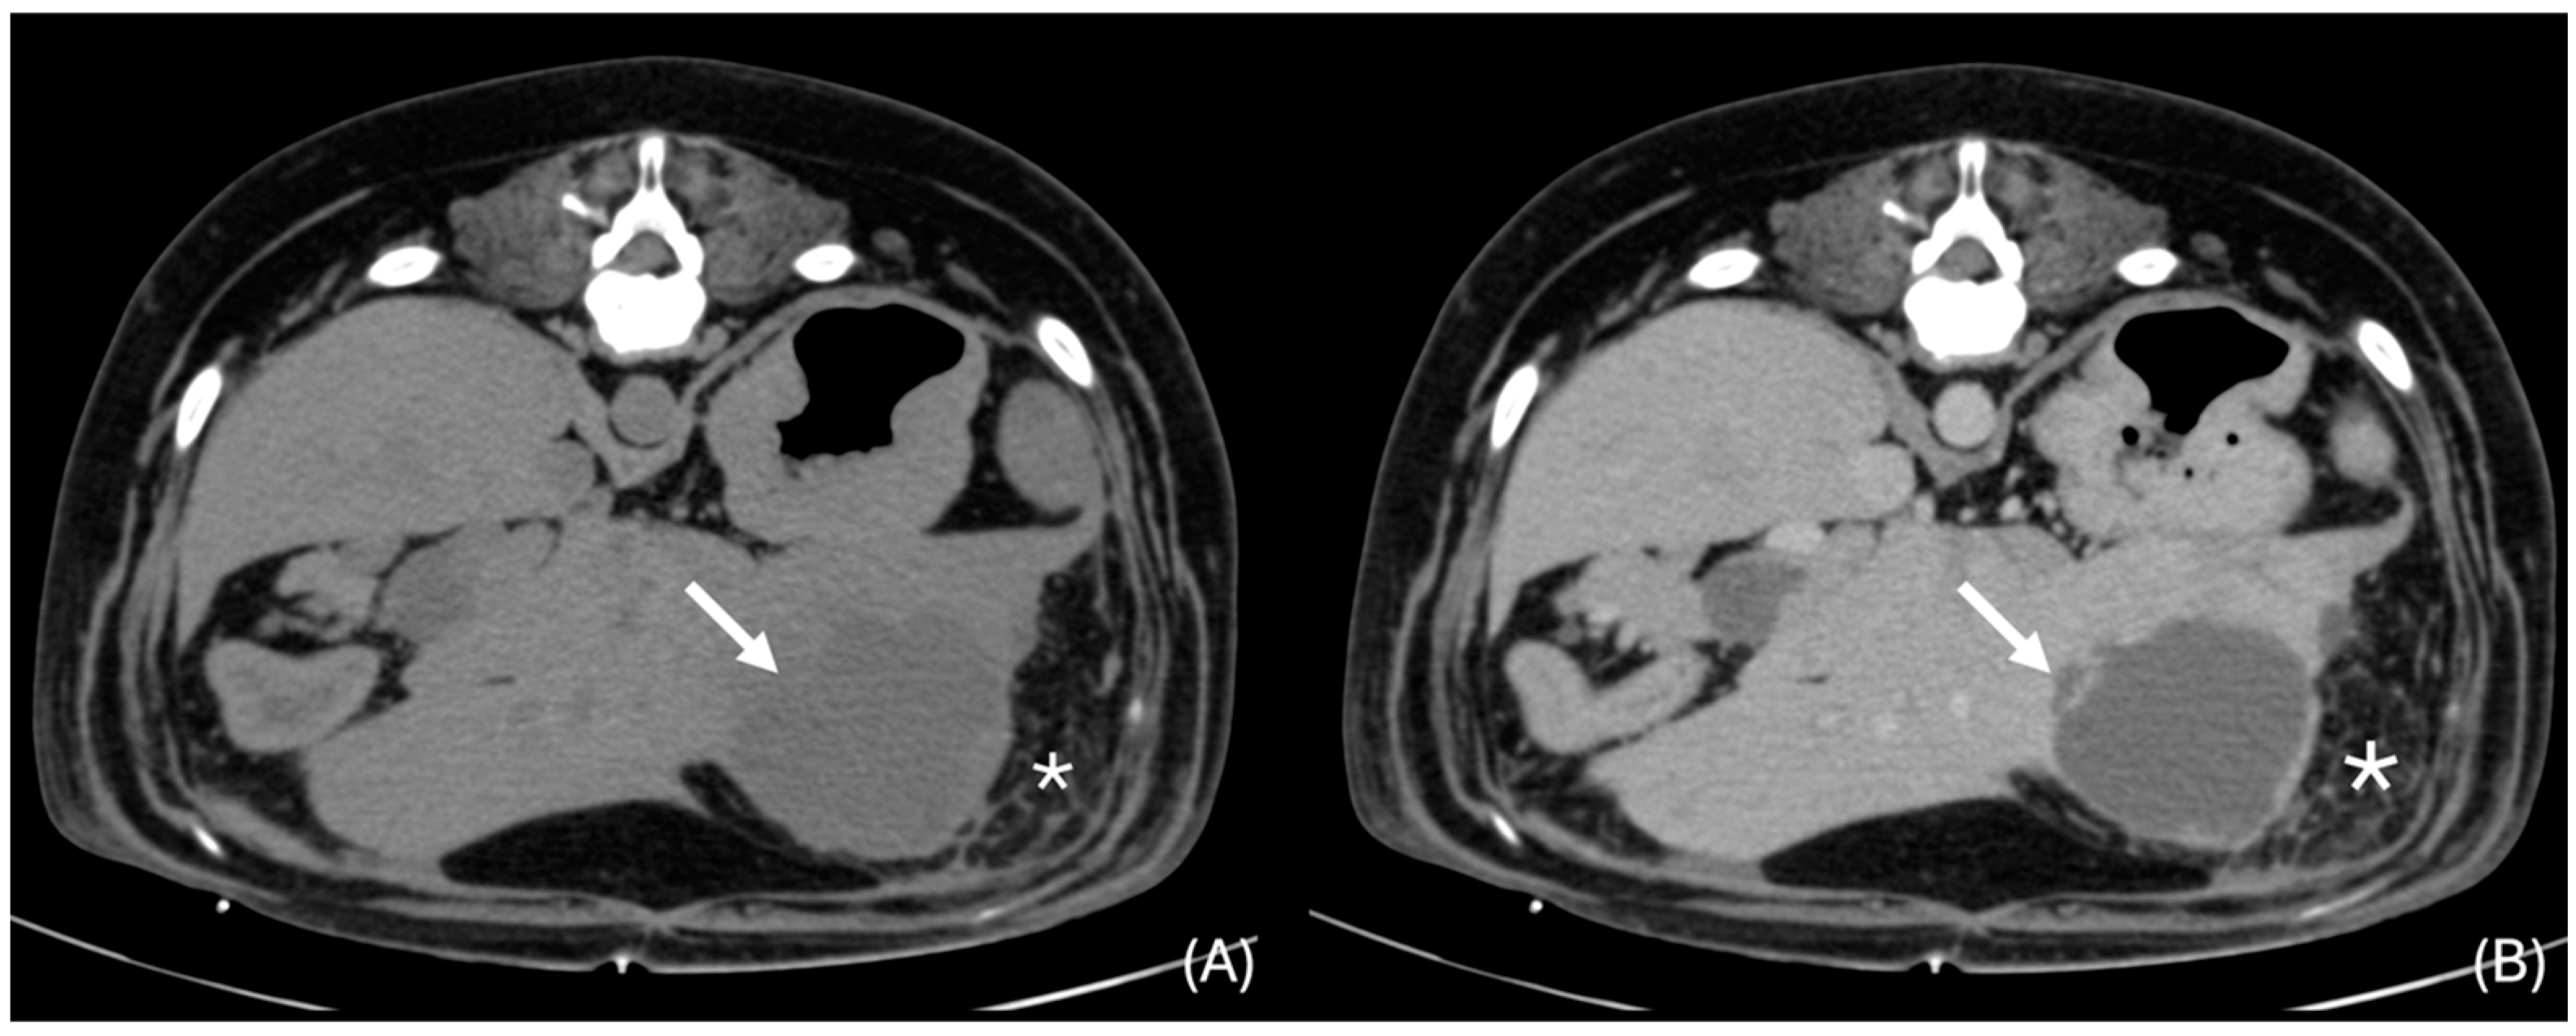

3.6.2. “Discrete” Changes